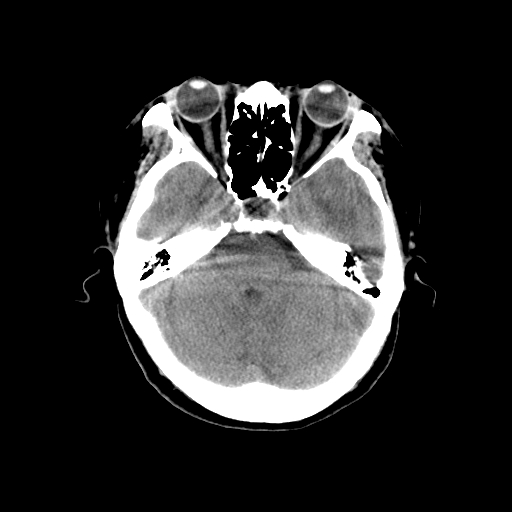

标题: CT14513:女性41岁,头部不适二月余,其它病史不详。请分析 [打印本页]

标题: CT14513:女性41岁,头部不适二月余,其它病史不详。请分析

1.考虑:左侧颞顶叶星形细胞瘤。2.大脑镰下疝。

支持!但楼主所提示处颅骨明显受压变薄,是否有合并蛛网膜囊肿或局部硬膜下水瘤的可能?脑穿通畸形暂不予以考虑:明显占位表现;病侧脑室无扩张;病灶不是较明确的脑脊液密度;边界不清晰。还是mri检查吧,提供的有价值信息更多一些,至少可以排除或肯定蛛网膜囊肿或局部硬膜下水瘤的存在。

1)考虑左侧颞顶叶胶质瘤。2)左侧颞顶部慢性硬膜下血肿?3)大脑镰下疝。